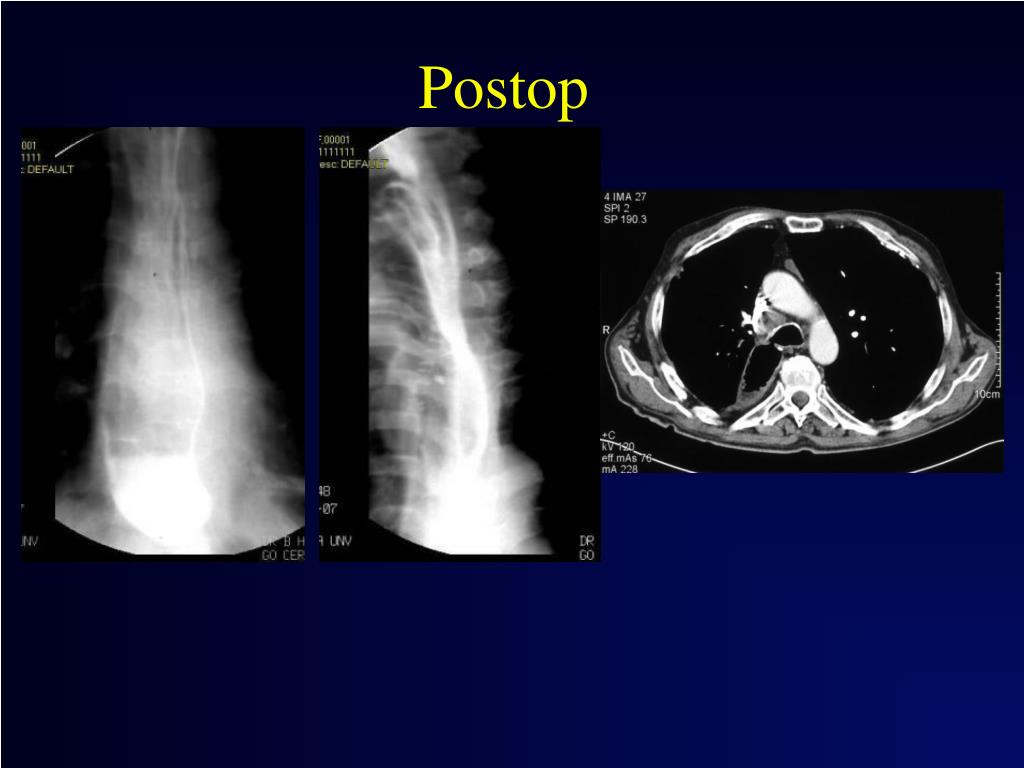

34. Postop